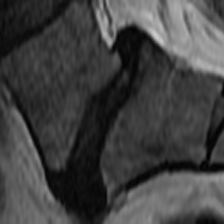

Lumbar Disc Degeneration (LDD) was found to be one of several reasons causing Low Back Pain [1]. Although there are several grading systems to quantify LDD, the Pfirrmann and Schneiderman scales are commonly used [2]. Pfirrmann et al. proposed a 555-scale grading system using T2-weighted MR imaging [3]. The grading system uses an algorithmic approach for LDD using signal intensity and disc homogeneity, demonstrated in Fig. 1. Over the past few years, several Deep Learning based methods were built to quantify LDD using MR imaging and the Pfirrmann grading system.

(a) PG 2

(b) PG 3

(c) PG 4

(d) PG 5

Fig. 1: Pfirrmann grades in L5-S1 as graded in the Northern Finland Birth Cohort dataset